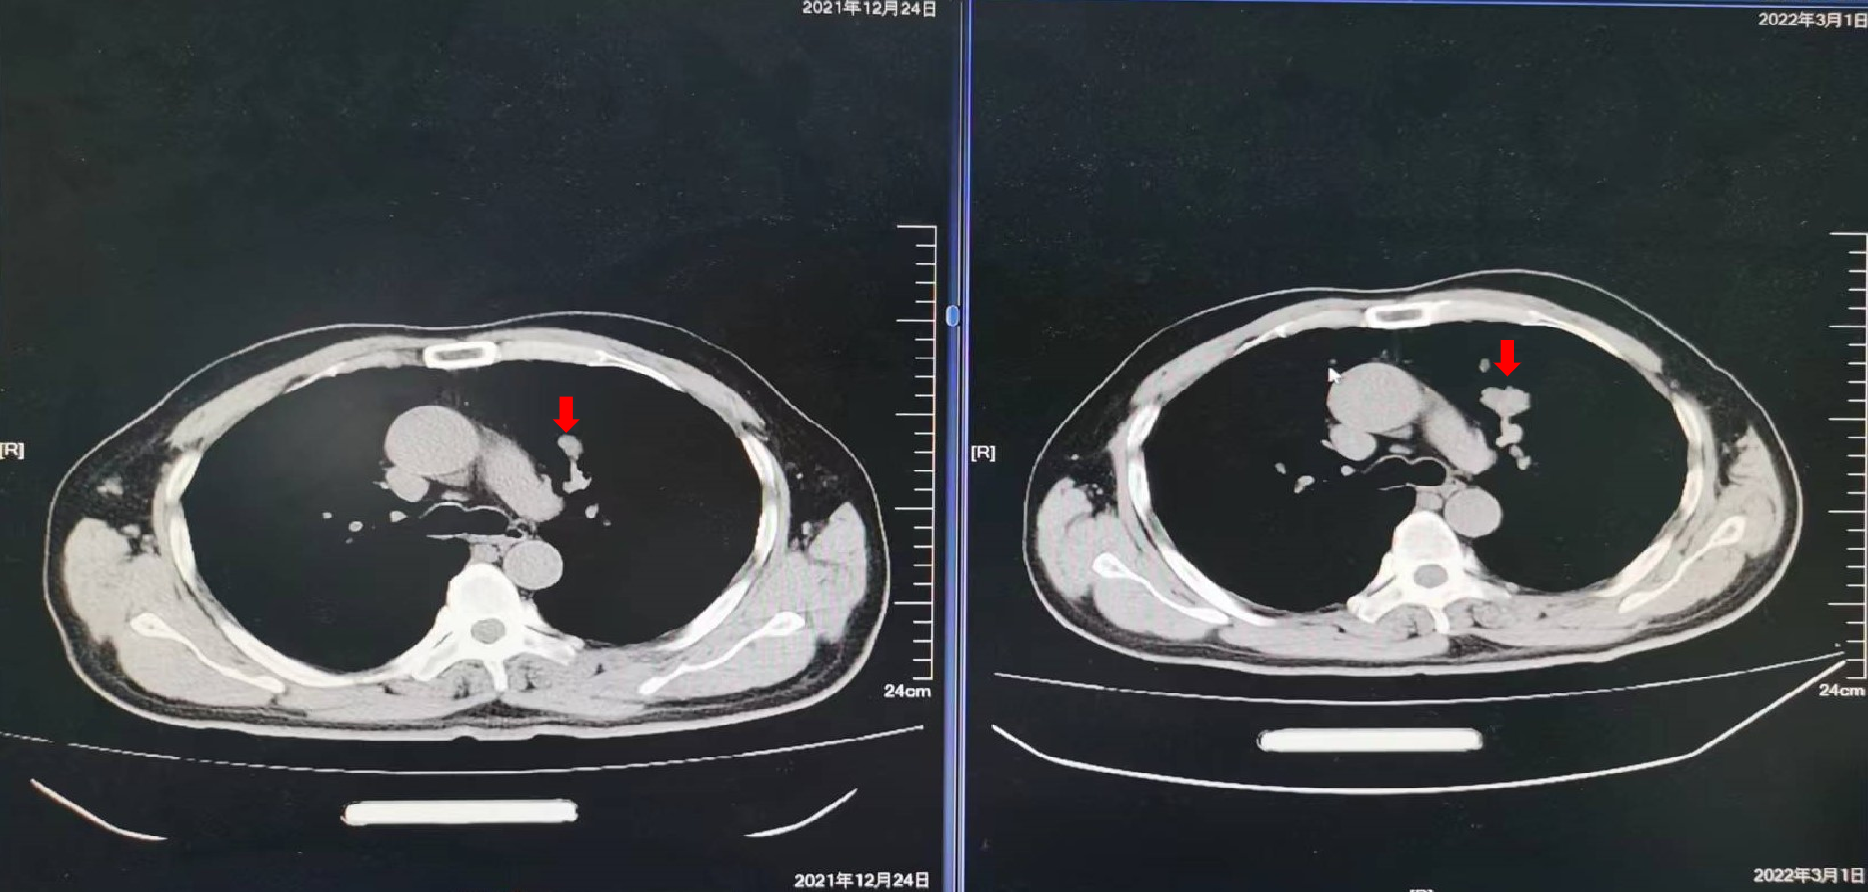

2019年10月16日:复查影像学检查提示新发肺转移,建议贝伐珠单抗,患者拒绝,继续XELOX方案化疗2周期,卡培他滨口服1周期,疗效为PD。

2021年5月27日:开始口服曲氟尿苷替匹嘧啶片(TAS-102)55mg每日2次 d1-5,d8-12,Q4W配合信迪利单抗免疫治疗。

疗效评价:SD,患者右腹股沟肿胀疼痛明显减轻,停用止痛药,PFS时间为10个月,主要不良反应为Ⅱ度骨髓抑制。